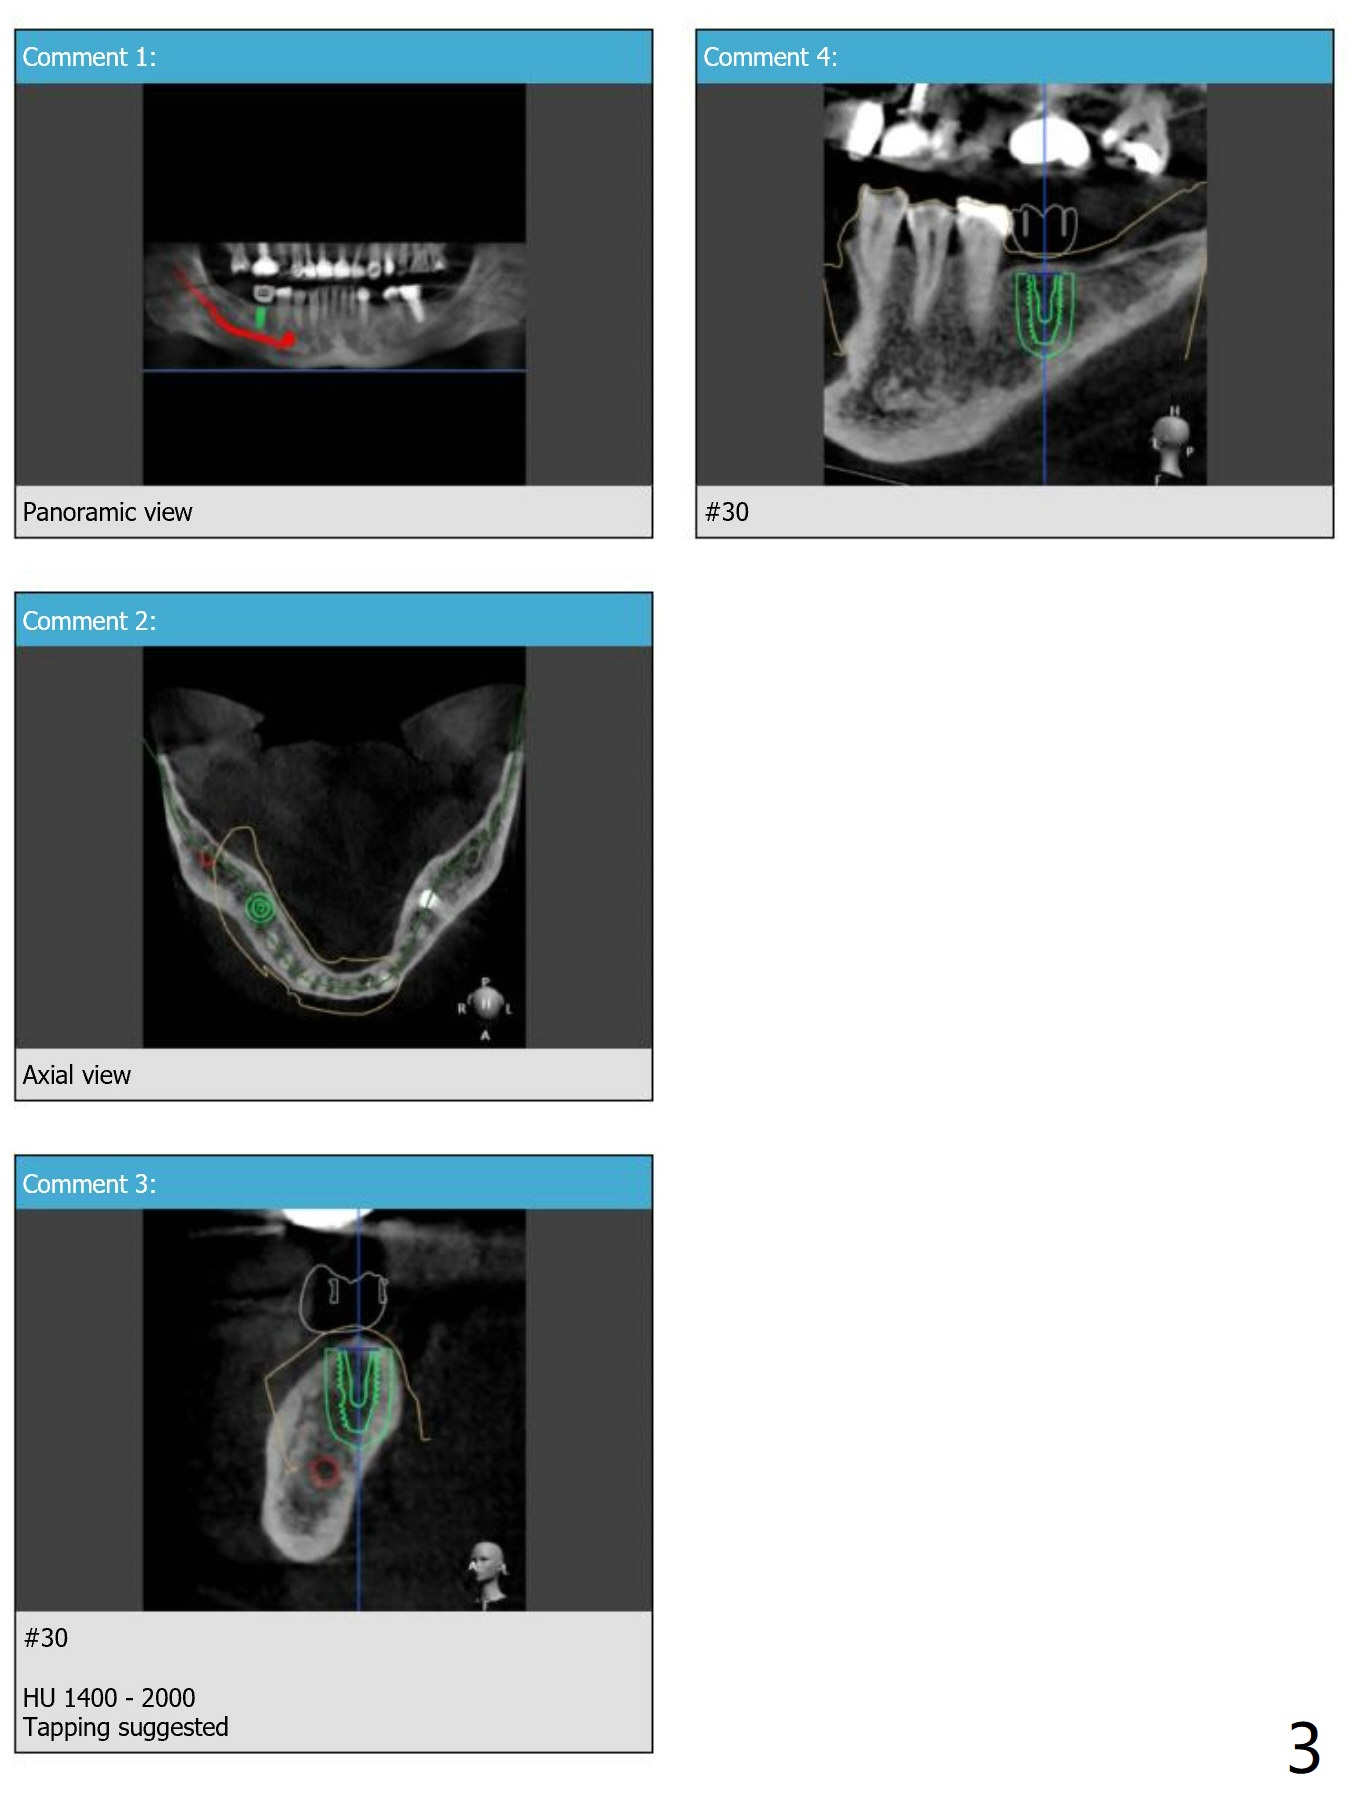

Guide Design for #30

Return to Lower Molar Immediate Implant, Armaments 30 Placement